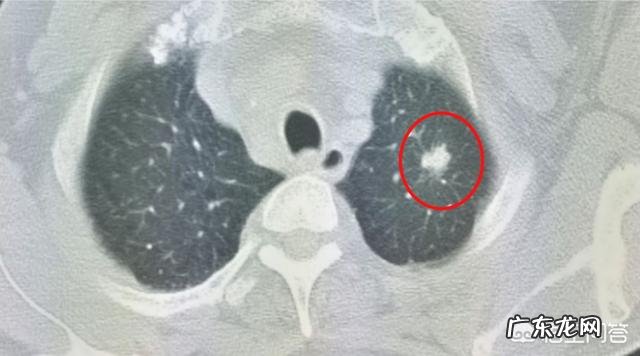

像这位女性患者,体检发现左下肺高危肺结节,以磨玻璃为主,随访观察了11年,最后一次发现有增大趋势才手术切除,病理是肺腺癌 。

这是名副其实的“懒癌”!